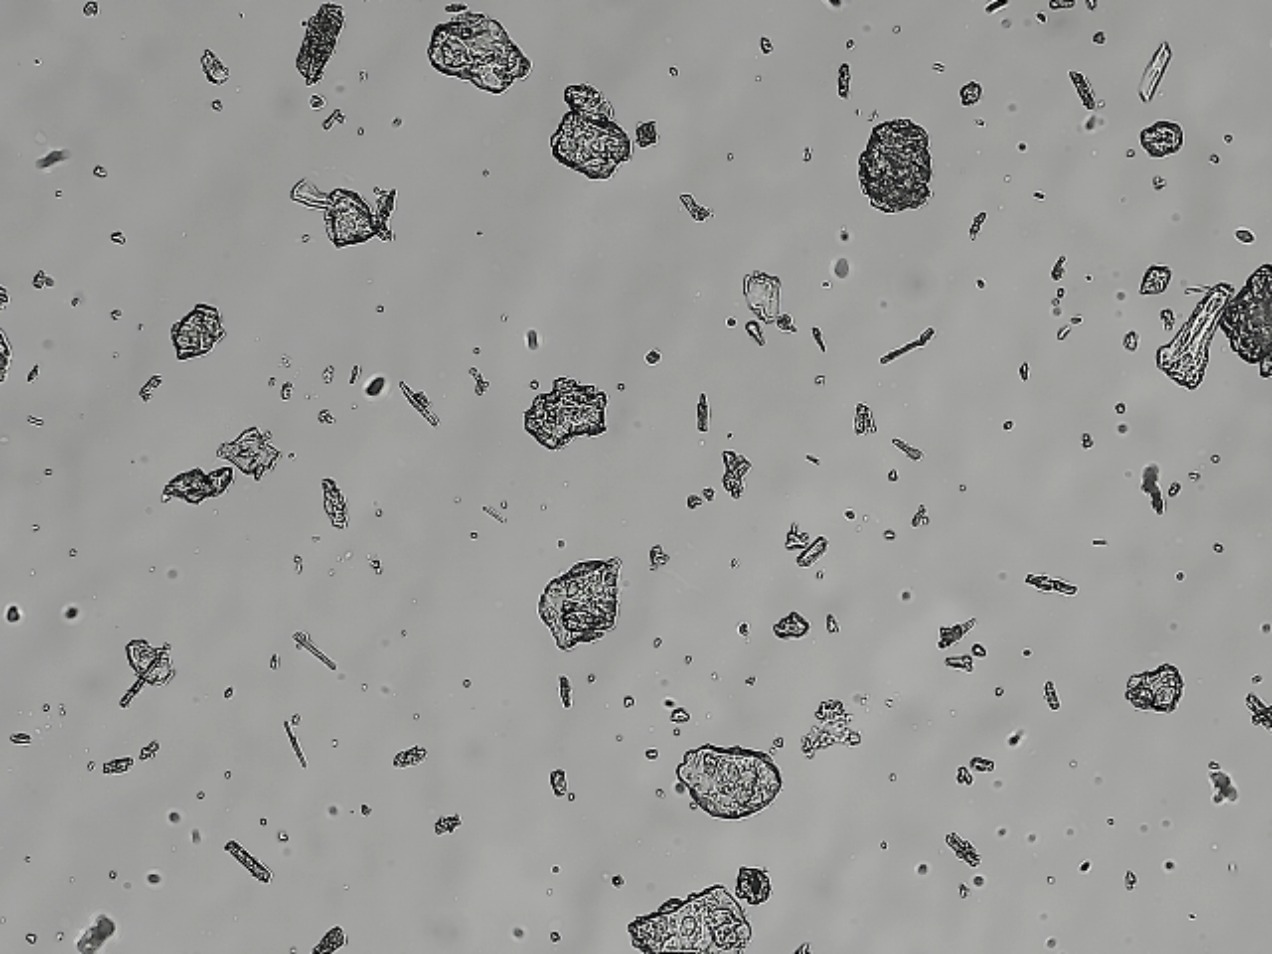

Comprehensive study of glass delamination and visible particulate in injections <790>